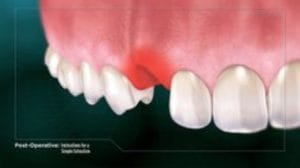

Family, Cosmetic, Sleep, Implants and Orthodontics Dental Clinic in 5710 Main Street Unit #3, Stouffville, Ontario, L4A8A9 serving Stouffville, Ballantrae, Musselman's Lake, Goodwood, Claremont, Uxbridge, Markham, Richmond Hill and the Greater Toronto Area.